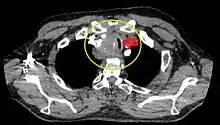

- Goitre comprimant la trachée cervicale.

Rétrécissement trachéal (flèche rouge). Tomodensitométrie (coupe transversale).

Même tumeur (coupe sagittale).